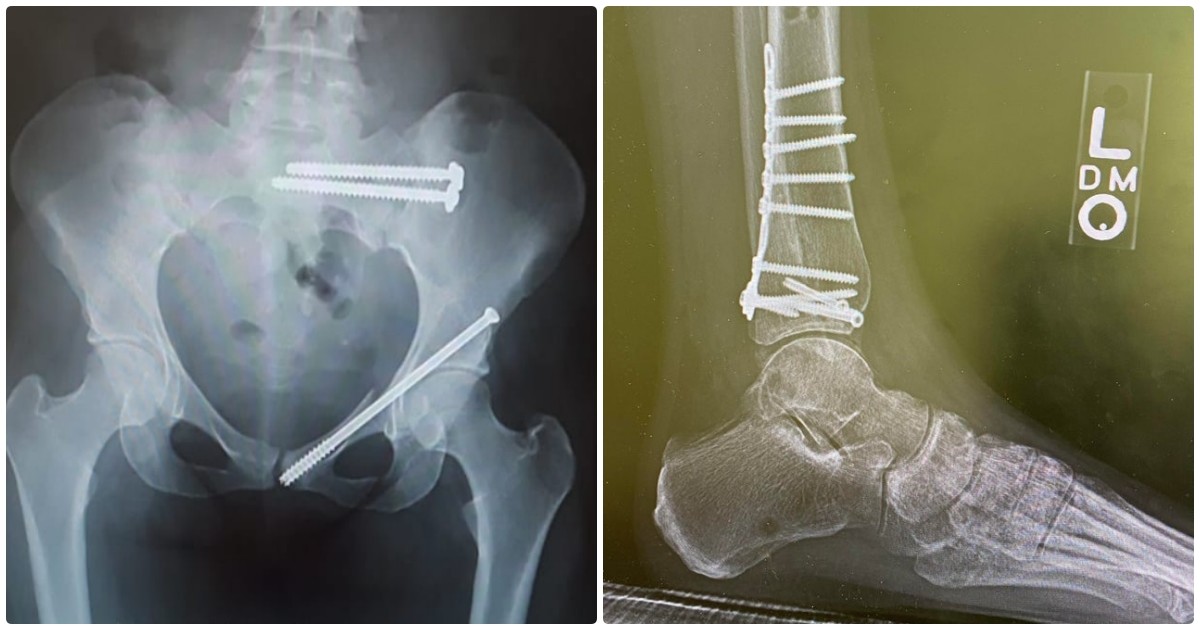

"Я упал в прошлую пятницу"

Слева - новое бедро

С ногой и шурупами, видел похожее фото. Друг на мяче поскользнулся, в результате такая же пластина и три шурупа. И год из активной жизни, сначала костыли, потом один костыль(с накладкой выше кисти), потом опять операция(снимали пластину) и по новой костыли, один костыль, потом палочка. Через год начал ходить сам, правда походка сильно изменилась, но хоть не хромает.

А вы последний раз когда делали снимок? Да вот 9 января сходил за хлебушком, поскользнулся и получил винтовой перелом голени. Потом Склиф, два дня на растяжке и операция. Две спицы в кости и через день свободен. Кстати гипс сейчас почти не накладывают.

ЗЫ. Понравились шурупы насквозь в берцовой.